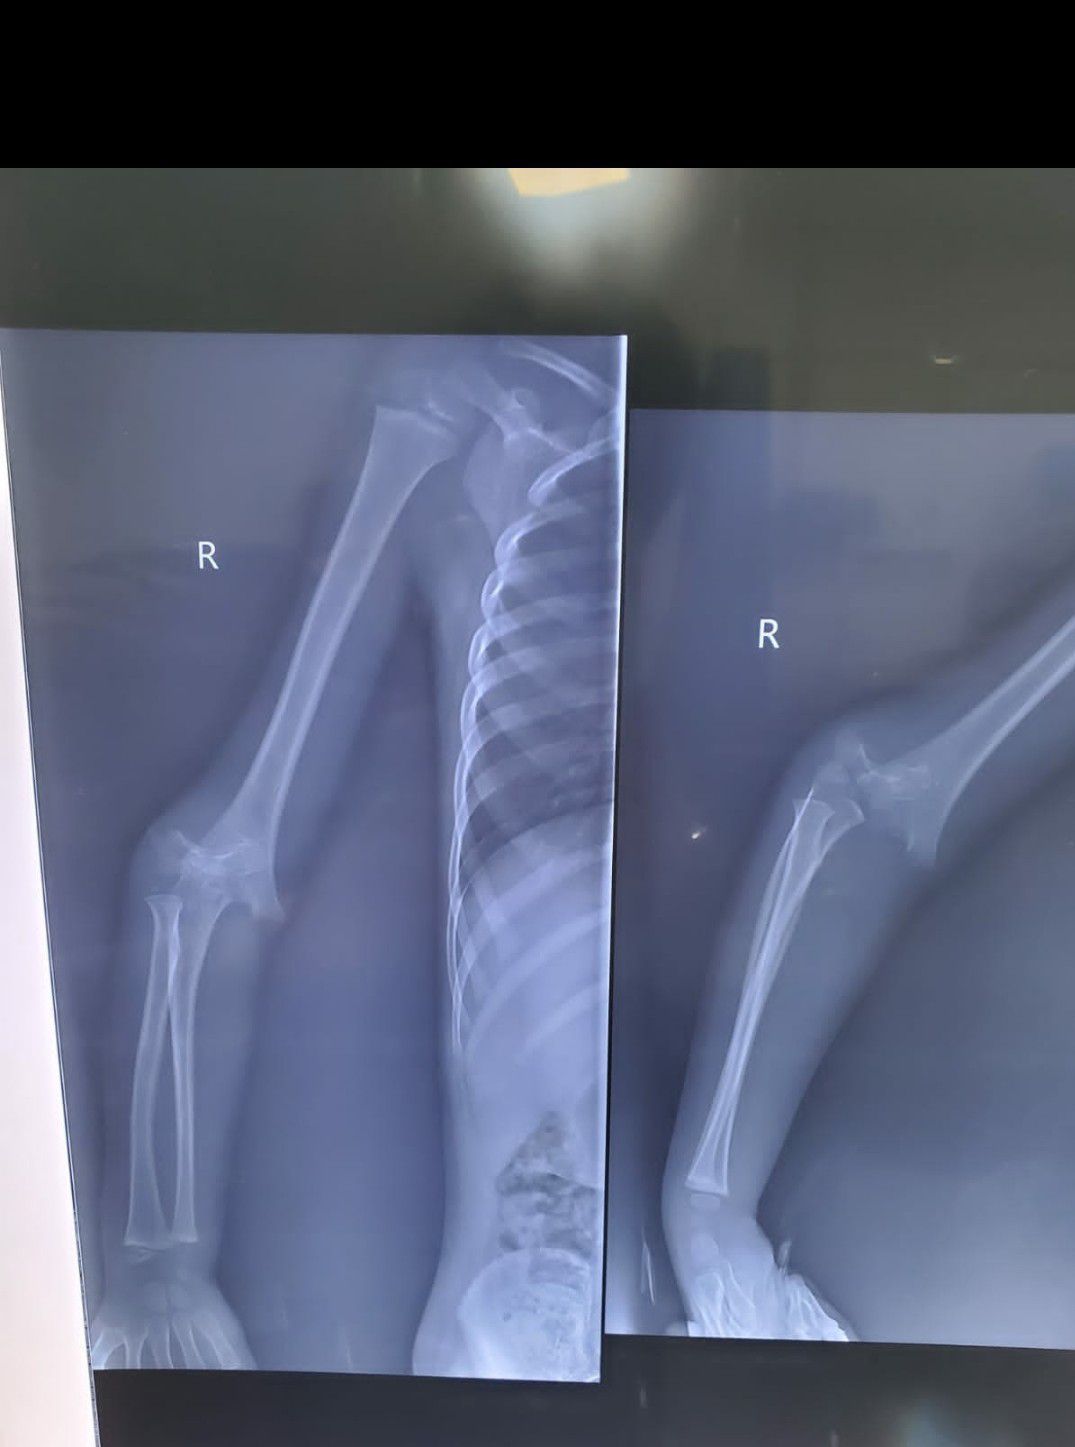

Radius(distal end) dislocation and Ulnar(distal end) fracture with displacement

Radius

Rta

Ulna

Paeds